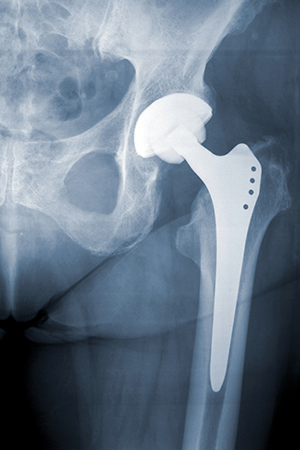

MHRA Updates Alert on Metal-on-Metal Hip Implants